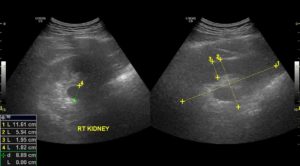

Как выглядит уплотнение в почках на УЗИ

Уплотнение почки – симптом, указывающий на изменения в эпителии, которым устлана внутренняя поверхность чашечно-лоханочной системы (ЧЛС).

Она представляет собой резервуар для сбора мочи, которая выводится в мочеточник через крупную лоханку в области почечного синуса.

При жалобах на тупые боли в пояснице, расстройства мочеиспускания (дизурию) врач-уролог или нефролог назначает ультразвуковое обследование органов мочевыделительной системы.

Изменение эхогенности ЧЛС указывает на их уплотнение. Если стенки собирательной системы утолщаются, интенсивность отражения ультразвуковой волны от их поверхности увеличивается. Во время обследования УЗИ-специалист обязательно заметит:

- изменение размера органа,

- неровность краев,

- неоднородность тканей ЧЛС,

- уплотнение лоханки,

- деформацию чашечек.

Почка покрыта паренхиматозной тканью, которая обладает невысокой эхогенностью. Но при опухолях или воспалении эхогенность увеличивается в разы.